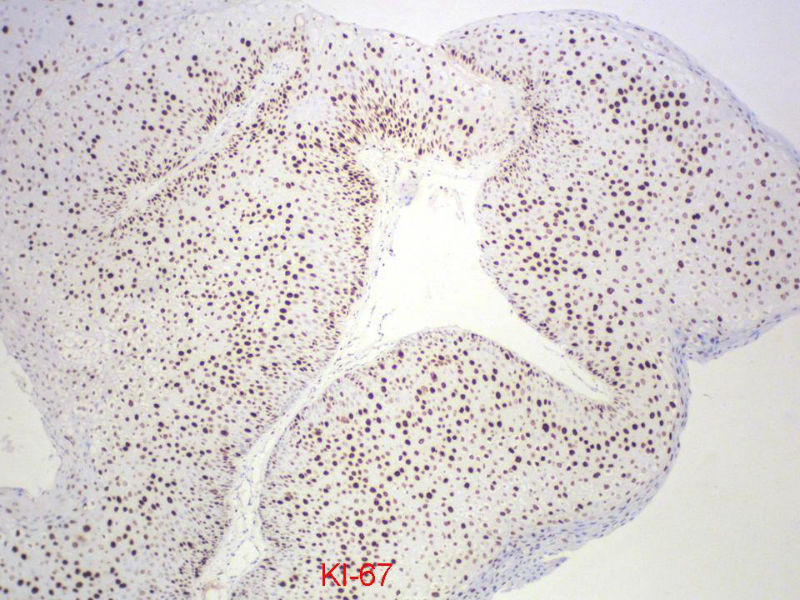

男,72岁,右耳听力下降两个月,检查右外耳道有黄豆大肿物,表面乳头状,手术切除。

您看了这样的免疫组化结果,会有什么样的考虑呢?